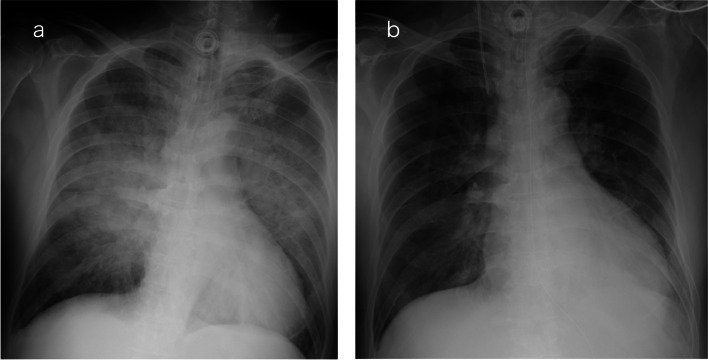

Background: Negative-pressure pulmonary edema (NPPE) often develops with upper airway obstruction, and is uncommon in secured airways, for example, after tracheostomy. Herein, we report two cases of NPPE post-tracheostomy.

Case presentation: Case 1: A 69-year-old man underwent prophylactic tracheotomy for possible airway obstruction secondary to glottic carcinoma. Two hours after awakening from general anesthesia, he had difficulty expectorating and developed NPPE due to airway secretions obstructing the tracheostomy tube. Case 2: An 11-year-old boy was admitted to the intensive care unit for continuous hemodiafiltration on a ventilator under sedation. On the 76th day, the day after the tracheostomy was performed, the patient developed patient-ventilator asynchrony due to sedative withdrawal syndrome. The postulated primary mechanism was functional airway obstruction due to patient-ventilator asynchrony.

Conclusion: These cases highlight the need to consider NPPE, even in patients with an airway secured with a tracheostomy.